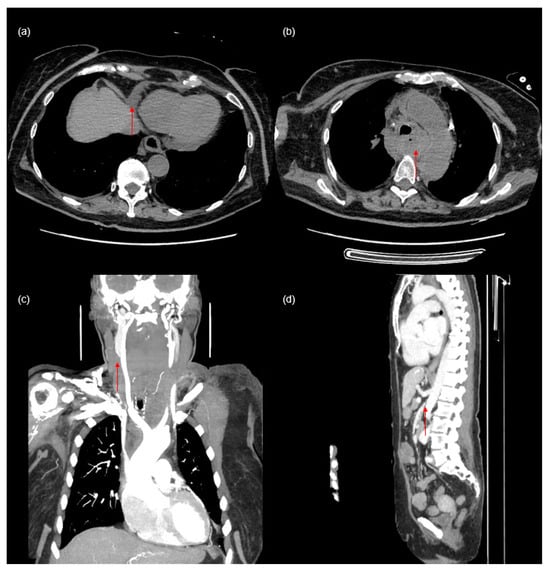

The aim of this report is to present a case of 72-year-old woman with end-stage renal failure due to glomerulonephritis. The patient was admitted to the hospital due to recurrent bleeding from a permanent dialysis catheter placed in the right common jugular vein, possibly caused by mechanical damage thus necessitating replacement. After an unsuccessful attempt to replace the catheter, a secondary catheter was placed in the left jugular vein. Immediately after catheterization, the patient, previously respiratory and circulatory stable, developed swelling of the neck and face. A chest X-ray revealed an abnormal CVC position (Figure 1a). A computed tomography (CT) study confirmed that the CVC followed a non-anatomical route and was seen on the left side, in the persistent left-sided superior vena cava (PLSVC), and entering in the coronary sinus (Figure 1b–g).

Figure 1. Posterior to anterior chest X-ray with a central venous catheter inserted into the persistent left superior vena cava (arrow in (a)). Persistent left superior vena cava in computed tomography ((bg)—arrows indicate the path that the catheter passed).